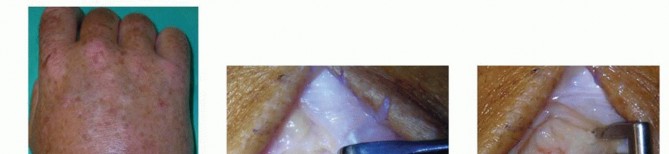

- Incision and Dissection: A 3-cm dorsal longitudinal incision is made centered over the affected MCP joint. Subcutaneous tissues are bluntly dissected to protect the dorsal sensory venous network.

- Extensor Mechanism Management: The extensor tendon is identified. To access the joint, the sagittal band is incised longitudinally on either the radial or ulnar side of the extensor tendon. The tendon is then gently retracted to the contralateral side using a Ragnell or Senn retractor.

- Capsulotomy and Debridement: A longitudinal capsulotomy is performed. Immediately upon breaching the capsule, purulent fluid will typically egress. Swab cultures should be taken at this precise moment if preoperative aspiration was unsuccessful.

- Irrigation: The joint is aggressively irrigated with a minimum of 1 to 2 liters of sterile normal saline. A small rongeur or curette is used to meticulously debride any fibrinous exudate, necrotic synovium, and debris from the articular gutters.